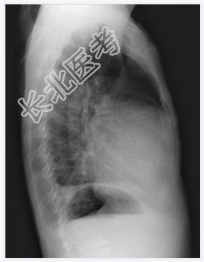

- [材料题] 患者,男性,51岁,腹胀1月余入院。查体:腹围增大,移动性浊音阳性。心界扩大,心音遥远。行胸部平片检查。

- 简答题1、诊断是什么?

- 简答题2、心包积液的常见原因有哪些?

- 简答题3、心包积液的典型临床表现是什么?